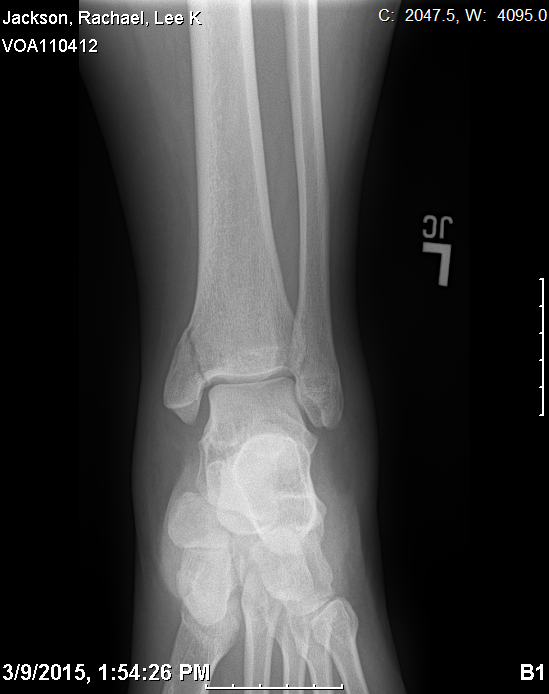

I broke my leg. I jumped off a climbing wall, and apparently the pad wasn’t enough padding, so I’m “non-weight-bearing” for 8 weeks post-surgery (the fracture was displaced, so they had to put pins in). It was and is a pretty sucky situation, but there have been a lot of things which have made it much better, and I think they’re worth noting.